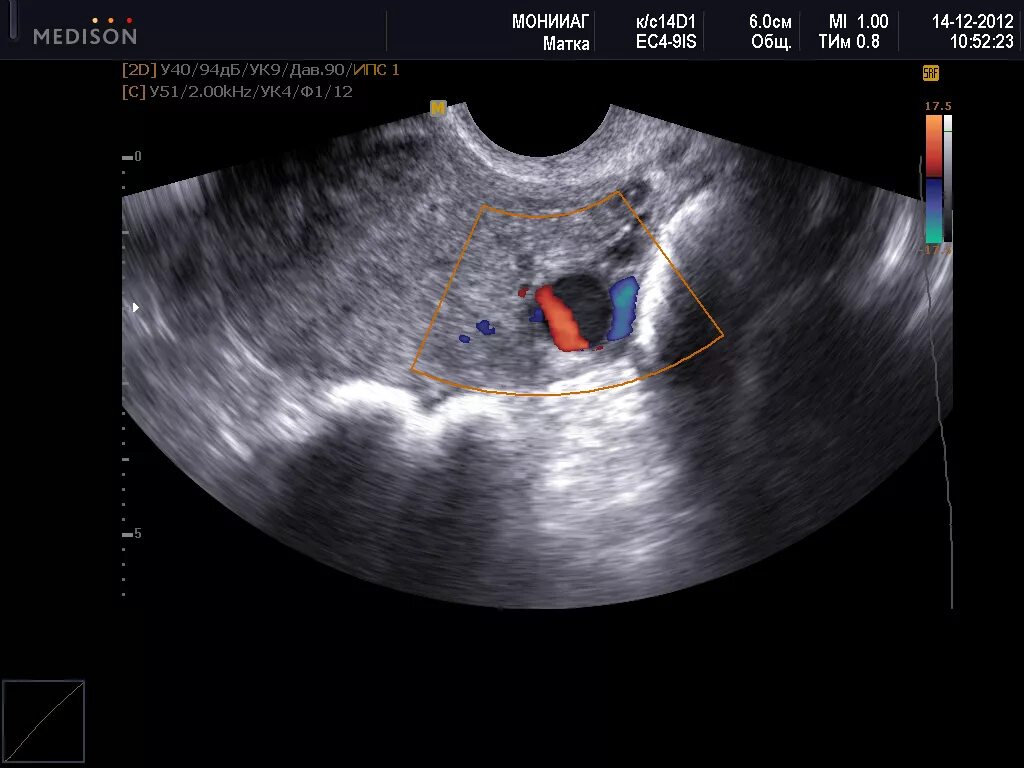

Эмбрион не прикрепился к матке причины